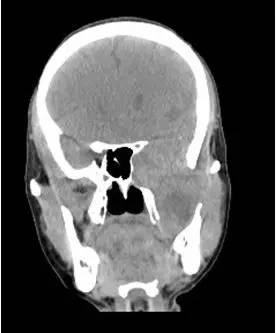

CT平扫冠状位重建

解析:本病例为中颅窝至颞下窝沟通性病变,对周围骨质主要呈膨胀压迫性改变,伴囊变、出血。

答案:C

病理:(中颅底内外沟通肿瘤) 神经鞘瘤,伴出血,局灶细胞较丰富。免疫组化结果显示:EMA(-), P53(-), S100(3 ), NF(-), PR(-), desmin(-), Ki-67( ,5-10%)

神经鞘瘤